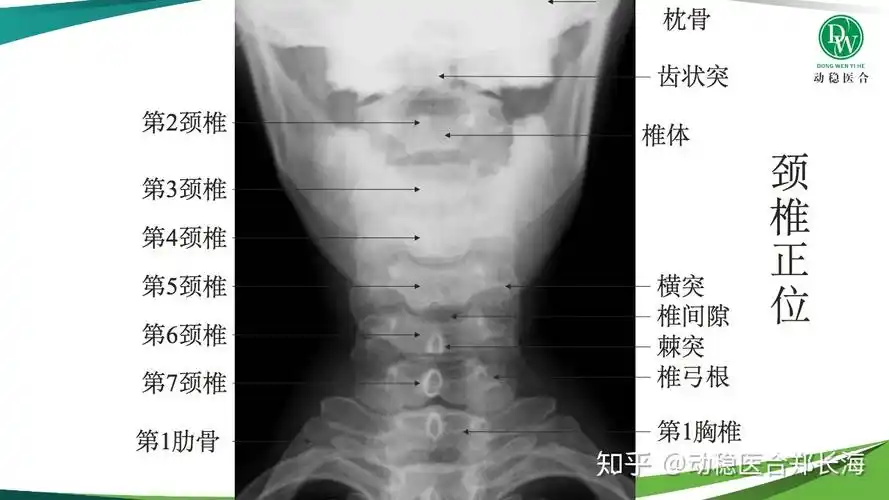

带你成为一个"知片"人 ——颈椎正位片

学习一下颈椎片!

我们先来看一张正常颈椎曲度的x光片.